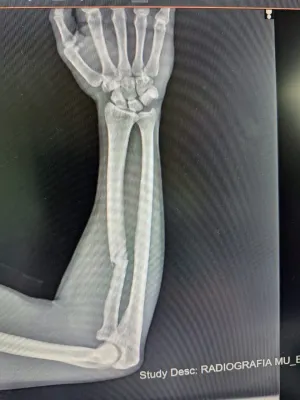

EXTRACTO SÍNTESIS O BAJADA: Rodrigo Díaz, de 20 años y oriundo de Ausonia, fue víctima de un violento asalto en Villa María que le provocó una fractura de radio. Su familia ha lanzado una rifa solidaria para recaudar fondos y costear la prótesis de titanio indispensable para su operación.

DESARROLLO PROFUNDO: El lamentable incidente tuvo lugar durante el pasado fin de semana largo, en circunstancias que aún se investigan en la ciudad de Villa María. Rodrigo Díaz, quien se encontraba en la ciudad, fue emboscado en un acto de violencia que le causó una seria lesión en su brazo. El diagnóstico médico confirmó una fractura de radio, una lesión que no solo es dolorosa sino que exige una intervención quirúrgica compleja con la implantación de una placa de titanio. Este componente, crucial para la correcta recuperación y funcionalidad del brazo, representa un gasto considerable que la familia de Rodrigo, de origen humilde, no puede afrontar por sus propios medios. Por ello, han decidido impulsar una rifa solidaria, con el objetivo de movilizar a vecinos y conocidos de Ausonia y Villa María, esperando que la generosidad de la gente permita reunir el dinero necesario para la operación y el proceso de rehabilitación del joven.